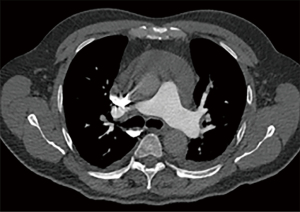

The pulmonary angiography revealed a right lobar/segmental PE (Figure 1) and a significant pericardial effusion (Figure 2) measuring 40 mm with a density of 15 HU. The patient was then admitted to the cardiology department for additional diagnostic evaluation. MSCT of the chest indicated enlarged paratracheal and subcarinal lymph nodes (Figure 3A,3B), while the MSCT of the abdomen showed no abnormalities. A transapical approach was utilized for the pericardiocentesis, during which 2.5 liters of hemorrhagic fluid were extracted and sent for cytological, microbiological, and biochemical examination. The subsequent results confirmed the type of exudative effusion, and the cytological examination indicated that there was intense and atypical growth of mesothelial cells. Thoracocentesis was subsequently performed and the analysis that followed corroborated the earlier findings. Due to suspicion of a systemic autoimmune disease or antiphospholipid syndrome, which could explain multisystem serositis (pleural and pericardial involvement), elevated inflammatory markers, thromboembolic event (PE), lymphadenopathy and constitutional symptoms, immunological tests were indicated.